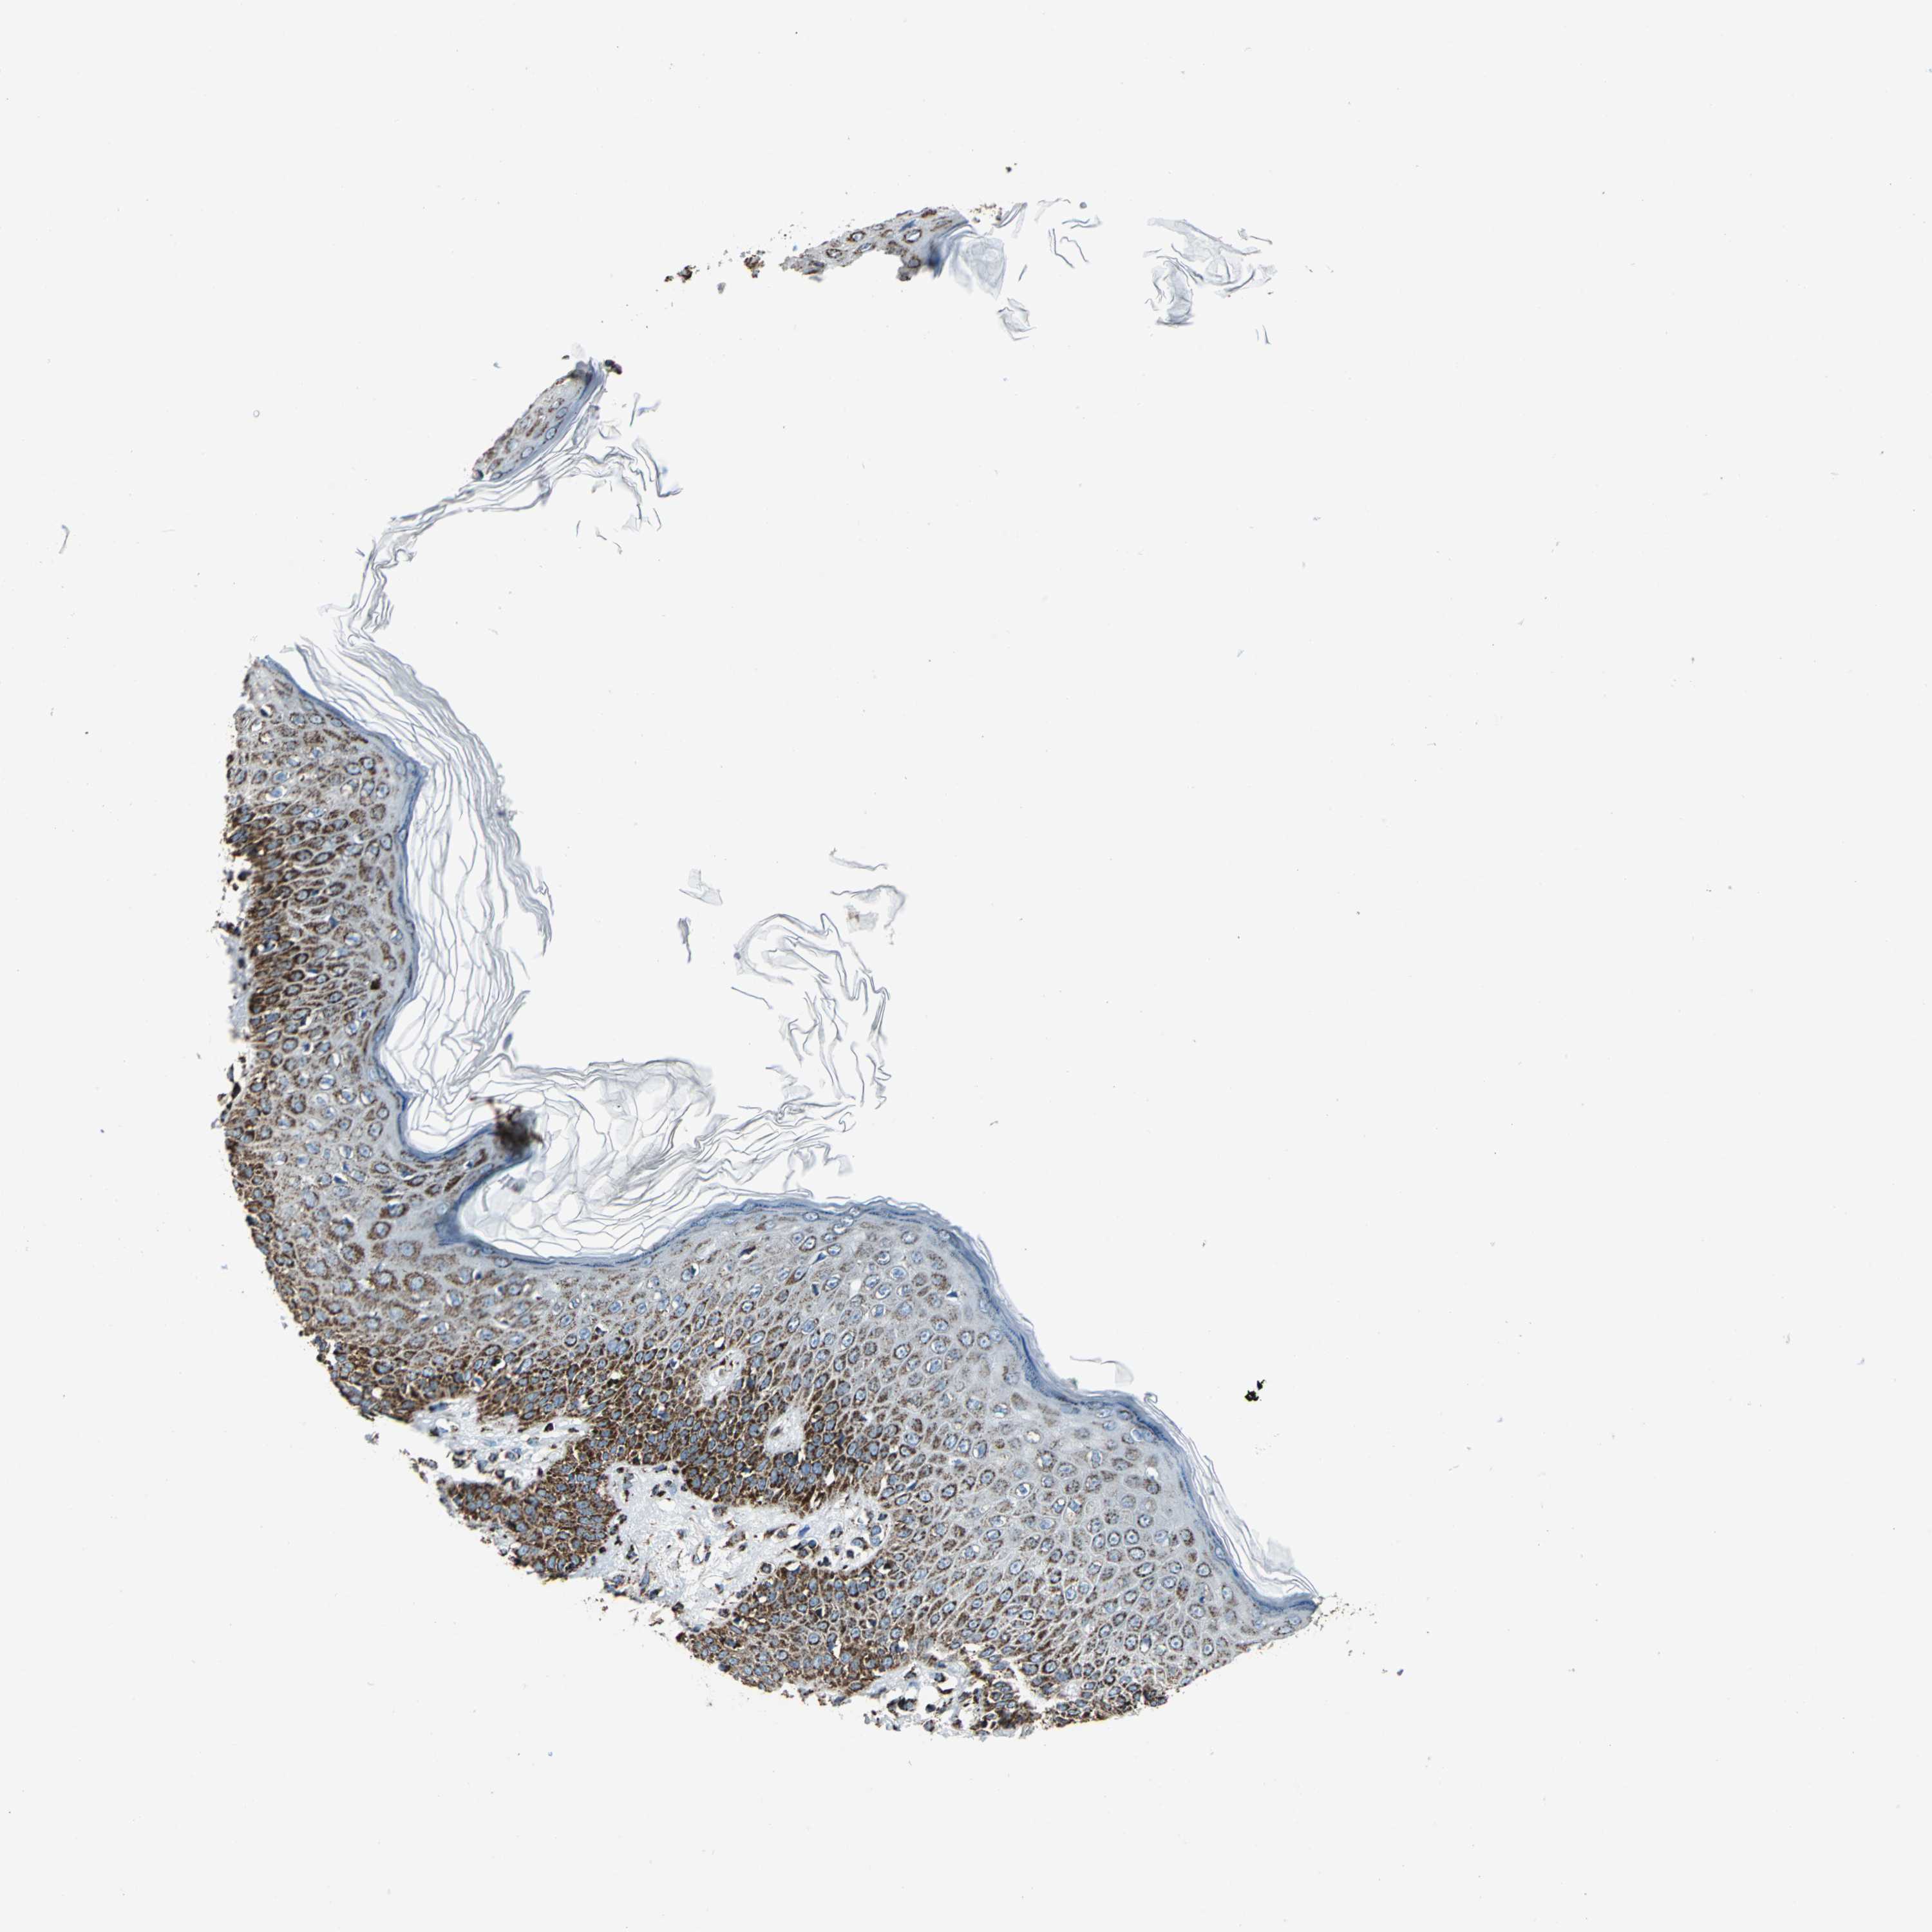

SKIN CANCER - Protein expressioni

A mouse-over function shows sample information and annotation data. Click on an image to view it in a full screen mode. Samples can be filtered based on level of antibody staining by selecting one or several of the following categories: high, medium, low and not detected. The assay and annotation is described here.

Antibody stainingi

Antibody staining in the annotated cell types in the current human tissue is reported as not detected, low, medium, or high, based on conventional immunohistochemistry profiling in selected tissues. This score is based on the combination of the staining intensity and fraction of stained cells.

Each image is clickable and will lead to virtual microscopy that enables deeper exploration of all samples and also displays staining intensity scores, fraction scores and subcellular localization as well as patient and tissue information for each sample.

Antibody HPA002907

Basal cell carcinoma